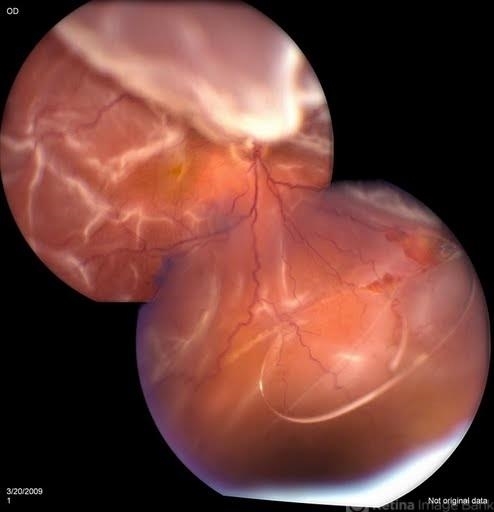

- chronic retinal detachment

- Jason S. Calhoun, Mayo Clinic Jacksonville, Florida

Fundus camera

TOPCON TRC 50-EX - Description

- 47-year-old male with trauma to the right eye. Patient had retinal detachment surgery in the past (scleral buckle), to the right eye. Patient came in with another retinal detachment with dislocated PCIOL lens. Notice the haptics tearing the retina. Patient underwent vitrectomy with gas exchange. VA was hand motion 1-day post op.